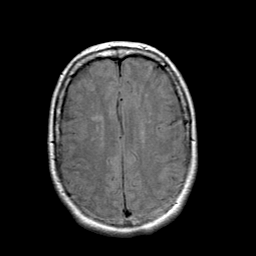

Stroke: proton density-weighted MR #1 -- Slice #18

[Home][Help][Clinical] Slice 18